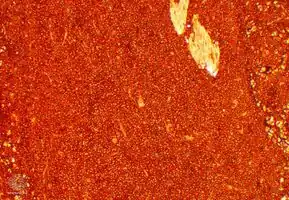

Micrograph of a plasmacytoma.

Micrograph of a plasmacytoma. H&E stain.